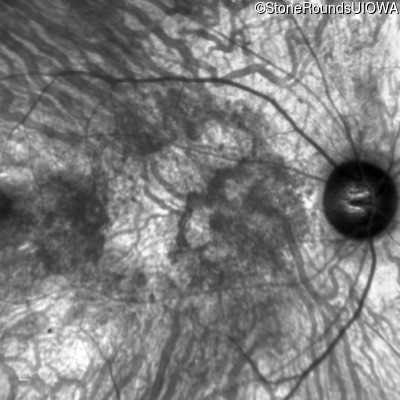

Infrared Fundus Photograph - Left - 10/225

Exemplar